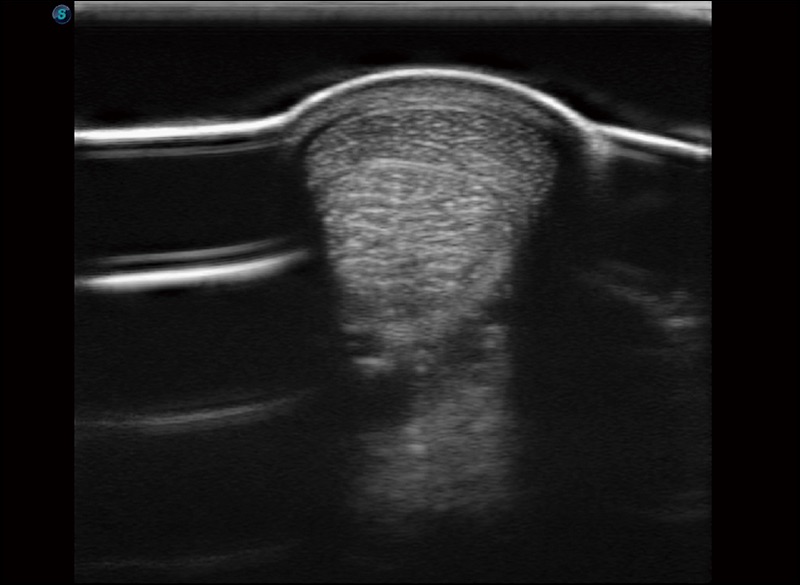

α1卓越的图像质量和便捷的工作流程,使每位宠物医生都能轻松扫查。其全面的兽用应用功能和紧凑型的结构设计,可以满足动物检查的多种需要。专业的预设检查模式和多领域测量软件包有助于为不同类型的动物提供检查, 让宠物医生能够出色的完成工作。